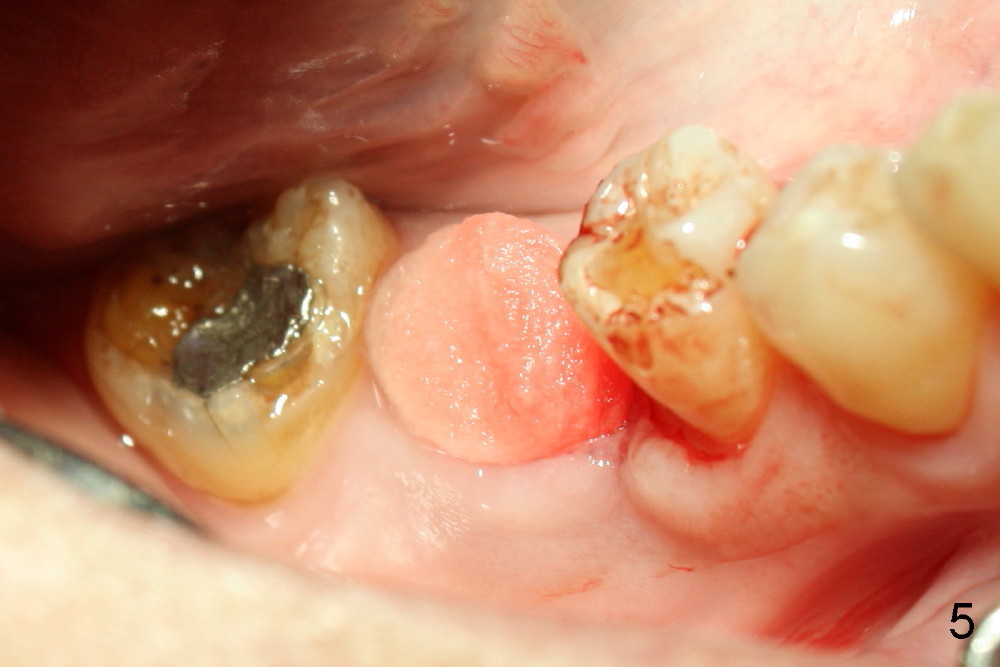

The tooth #30 was extracted in other office 1 month ago. The socket appears to heal normally. A tissue-level implant is placed as planned and smoothly. No antibiotic is prescribed pre- or post-op. The patient reports mild pain 1 week postop. There is a sign of infection. Amoxicillin is prescribed. One week later, the symptom improves, but the infection signs are present (Fig.1). The implant has mobility and is removed (Fig.2). The osteotomy is thoroughly debrided, followed by copious irrigation with normal saline and Clindamycin soaking. Irradiated cancellous bone graft (.5 mg) is placed (Fig.3,4). The wound is covered by collagen plug (Fig.5) and sutured with Chromic gut (Fig.6). Amoxicilin is prescribed postop. One week follow up reveals normal wound healing (Fig.7 (buccal view), 8 (lingual)).